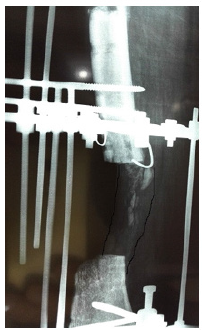

A male aged 60 had motor vehicle accident and sustained open fracture (Gustilo and Anderson type 3 b) of the tibia. Initially, he managed in another hospital with unplaster external fixator with screws in tibia and Kirschner wire in fibula. As there was skin loss so flap was applied over it. A few days late the flap was failed and there was pouring pus coming out of wound. In the first step he was referred to infective medicine unit of our hospital for infection control. A lot of antibiotics has been tried but insane. They have requested our unit for help in managing to eradicate infection. All antibiotics were stopped debridement with wound excision was done but it did not heal. Then all the implants were removed and daily dressing was advised to control infection but no improvement. Finally a resection of the nine centimeter of infected segment of bone done with application of Ilizarov fixator proximal osteotomy for bone transport. No antibiotics were used in this procedure. Skin loss were coverd without any procedure after application of Ilizarov that controlled the infection. With Ilizarov there is darmatotaxis which cover the skin loss. After few follow ups of bone transport the patient felt severe pain when he rotated the nuts. On examining the patient, everything was found normal except the lateral radiograph, which showed the transporting bone was deviated from its path. Deviation was corred with horizontal rods while the transport was stopped. In the next follow up visit we saw new bone formation within the gap. We stoped everything for the gap to be healed spontaneaouly without transport. In this patient, a 5 centimeter bone has been transported (Figures 7-12).